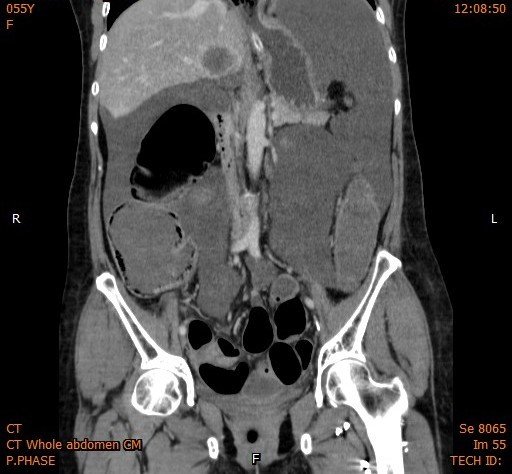

• Although pneumatosis coli can be seen on abdominal radiographs, CT is the most sensitive imaging test for identification

Abdominal CT images

Answer : C. Air in the bowel wall or pneumatosis intestinalis

This case show curvilinear gas in the cecal wall